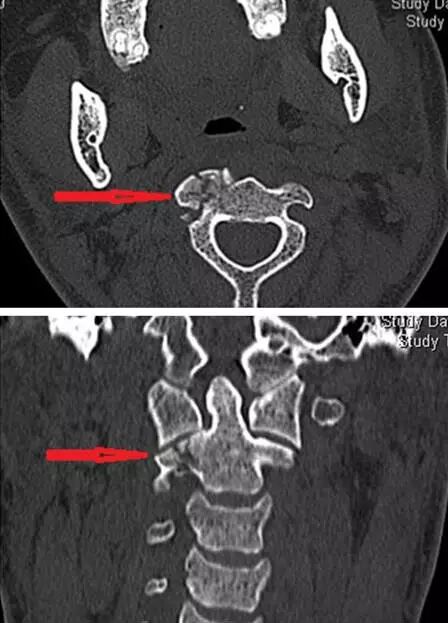

旅游大巴失控撞隧道导致21人受伤,车祸中,福州一名30多岁女子叶芳(化名)颈椎两处骨折,腰椎爆裂,不能动弹。由于伤情太重,当地医院把她转诊到省立金山医院。我科立即对叶芳进行全面病情评估,积极手术准备,诊断为:颈2粉碎性骨折,颈6椎板骨折,腰1椎体爆裂性骨折。

颈髓是仅次于大脑的神经中枢,决定呼吸、心跳、活动、感觉。创伤后的骨折、出血、水肿等随时可能损伤颈髓,引起瘫痪甚至死亡,手术刻不容缓。同时手术难度也是巨大的,固定高颈段的骨折堪称骨科手术的巅峰,颈椎第一、二节的椎弓根也就5毫米粗,而固定用的钢钉有3.5毫米,必须精准无误地钉进椎弓根内,往外1毫米,伤及椎动脉,往内1毫米,伤了脊髓,手术都算是失败的,甚至危及生命。